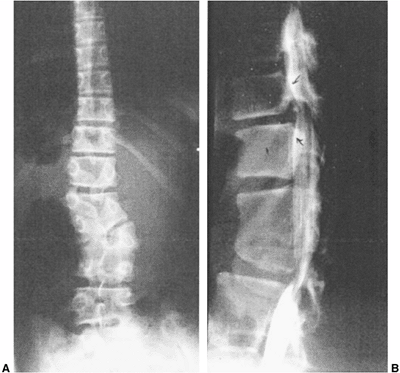

Figure 19.5

Congenital kyphosis (type I by Winter classification) with posterior hemivertebra. Neurologic function has regressed from normal to paraplegic by 9 months of age, the time of this computed tomography (CT) myelogram image. Anterior decompression and stabilization were needed. |